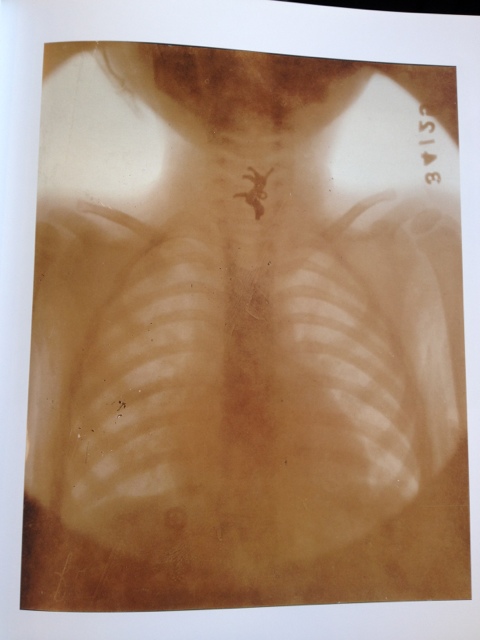

July 12, 2012July 12, 2012 Toy dog in esophagus share the love: Email a link to a friend (Opens in new window) Email Share on Facebook (Opens in new window) Facebook Share on Tumblr (Opens in new window) Tumblr Share on X (Opens in new window) X Share on Pinterest (Opens in new window) Pinterest Like Loading... Related